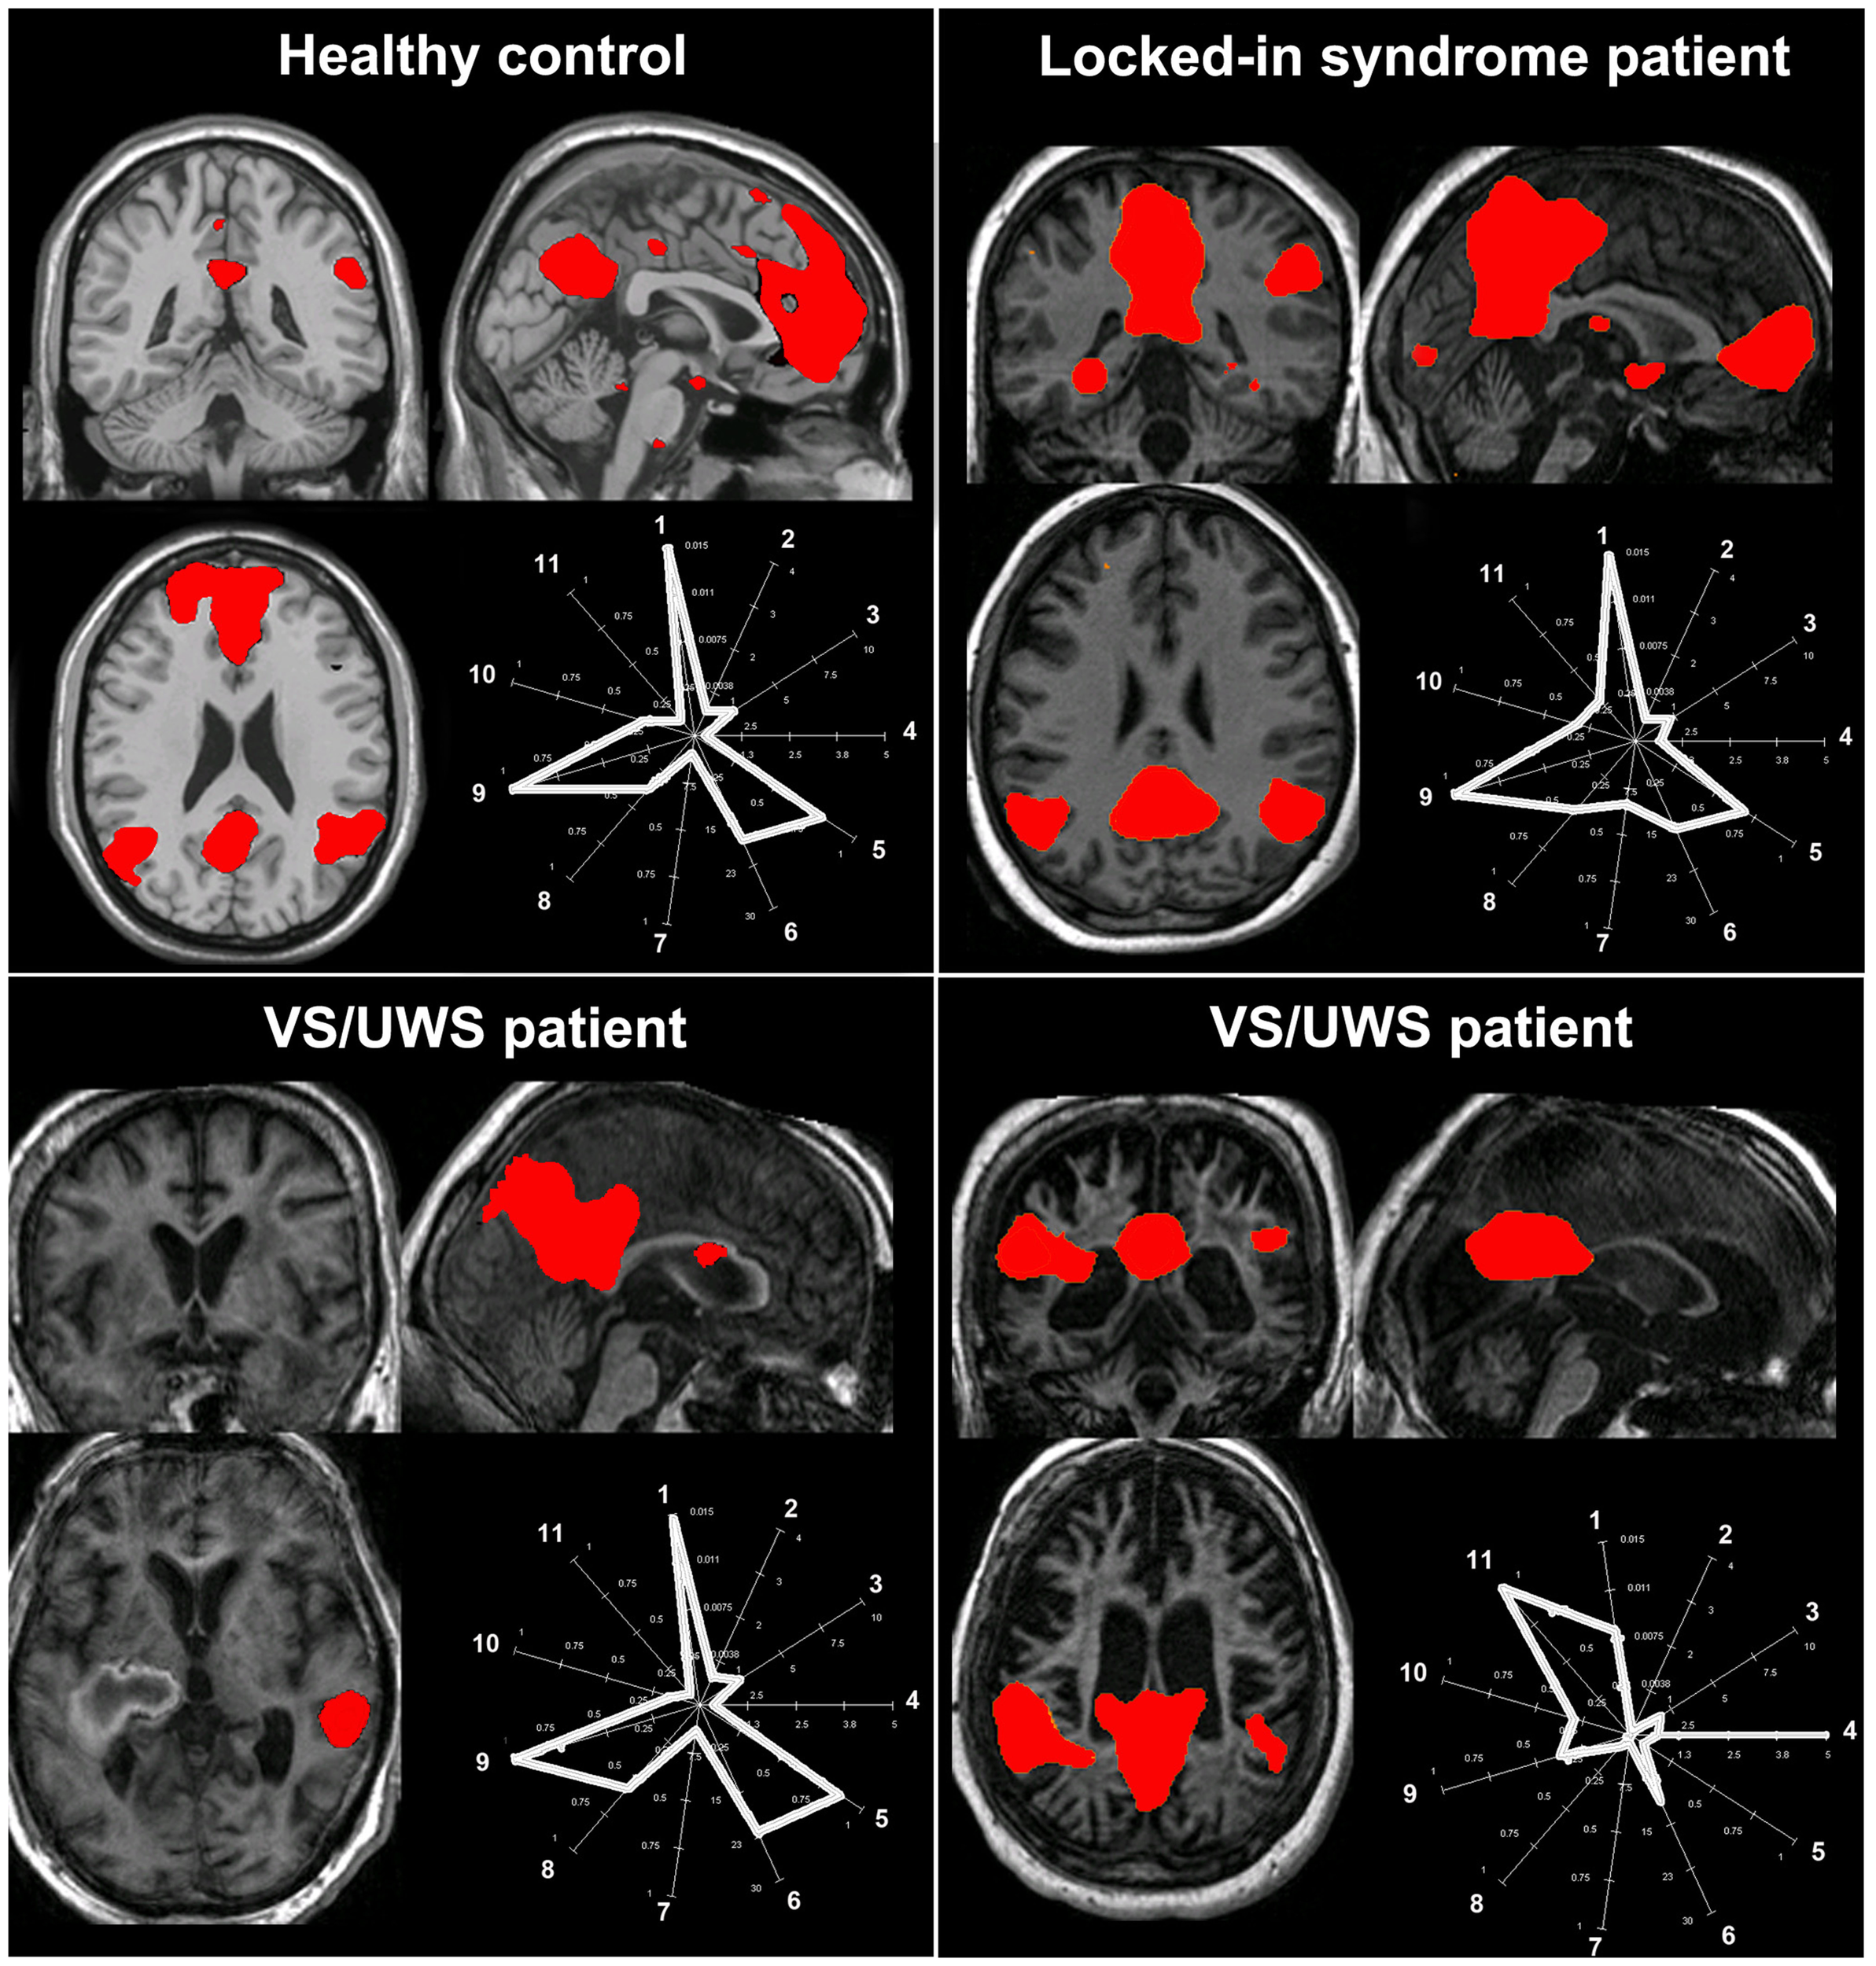

Data-driven methods are used to analyze whole-brain connectivity patterns without the need of a priori seed regions. ICA is the most widely used methodology with high level of consistency in results within subjects (van den Heuvel and Hulshoff Pol, 2010). ICA divides an entire dataset into different maximally statistical independent components and thus is able to isolate cortical connectivity maps from non-neural signals (Beckmann et al., 2005). Spontaneous activity is therefore automatically separated from noise, such as head motion or physiological confounds (e.g., cardiac pulsation, respiratory, and slow changes in the depth and rate of breathing; Beckmann and Smith, 2004). This method has the advantage that it can evaluate and compare the coherence of activity in multiple distributed voxels (Cole et al., 2010). The advantage is that it divides different RSNs into different components. However, ICA does not provide any classification or ordering of the independent components. It is therefore perceived as more difficult to understand due to the complex representation of the data. The most straightforward method for labeling the components is by visual inspection, but this lacks reproducibility and could be hard to perform in cases with a large component dimensionality. Alternatively, an automatic selection is preferable but the way to choose the right independent component remains a delicate issue. By merely performing a spatial similarity test with a predefined template has been shown not to be successful for choosing the right component (Soddu et al., 2012). Some automatic approaches for component selection have been proposed, based on template matching using the “goodness of fit” as an outcome index. However, these methods have to be interpreted with care especially in cases of deformed brains as in patients with a traumatic brain injury or comatose state. It was recently proposed that when selecting independent components in patients populations, spatial, temporal, and a “compromise” between spatial and temporal properties of the network of interest need to be met (Soddu et al., 2012). For example, a component can be erroneously selected as the RSN of interest if the selection is based on the spatial pattern ignoring the properties in the time domain (Figure 3, bottom right panel). Additionally, the determination of the proper dimensionality (i.e., the “right” number of estimated components) remains unclear. Extracting many components can result in the spatial segregation of the network of interest into multiple sub-networks (Smith et al., 2009). It was shown, for example, that the use of 75 components can reduce the DMN into four components and the sensorimotor network in six (Allen et al., 2011). When applying ICA in pathological brains it is probably more useful not to select a large quantity of components, because high component dimensionality can further reduce the chances of identifying a network due to decrease in spatial pattern and spectral properties (Tohka et al., 2008).

Figure 3. The challenge of selecting the “right” independent component as the resting state network of interest in pathological conditions. The figure illustrates the spatial pattern (brain maps, z values 0.8–10) and spatial-temporal properties (fingerprints: a representation of the component in a multidimensional space of parameters; De Martino et al., 2007) of the default mode network in healthy consciousness states (healthy subject, patient with locked-in syndrome; upper row) and in two patients with vegetative state/unresponsive wakefulness syndrome (VS/UWS; lower row). For the healthy control, the locked-in syndrome and the VS/UWS patient in the lower left corner, the default mode network shows the characteristic properties in both the spatial and the temporal domain (i.e., the fingerprints pick in the 0.02–0.05 Hz frequency band labeled with the number 9) even if for the VS/UWS patient the spatial pattern is only partially preserved. Of note is that the second VS/UWS patient exhibits the spatial pattern of the default mode network but importantly the time course of this component is characterized by high frequency fluctuations, in the 0.1–0.25 Hz frequency band and high spatial entropy (labeled, respectively, with the number 11 and 4 in the fingerprint). Therefore, such activity cannot be considered of neuronal origin. As a consequence, if the component selection was merely based on a spatial similarity test (e.g., with a predefined template), then this component could be erroneously selected and further statistically analyzed. A “compromise” in the selection of the appropriate network of interest in the space and time domain is needed to will eventually exclude non-neuronal contributions [Fingerprint labels: (1) degree of clustering, (2) skewness, (3) kurtosis, (4) spatial entropy, (5) autocorrelation, (6) temporal entropy, power: (7) 0–0.008 Hz, (8) 0.008–0.02 Hz, (9) 0.02–0.05 Hz, (10) 0.05–0.1 Hz, (11) 0.1–0.25 Hz].